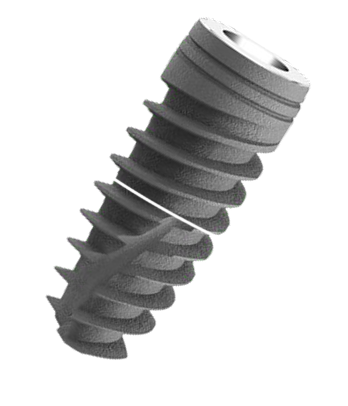

Advanced EV Implant System

Designed for immediate load

with functional Prosthesis.

Shorter Time to Teeth.